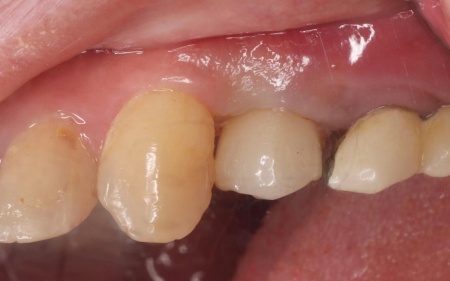

| 診断 | 拝見したところ、左上奥歯(第1小臼歯)は歯の上の部分である歯冠が折れ、歯根のみ残っている状態でした。 また、左下奥歯(第2小臼歯)には被せ物が装着されています。 レントゲン撮影をして痛みの原因を詳しく検査したところ、左上下奥歯の歯根が割れており、その影響で痛みが出ていると考えられました。 歯根が割れた歯は温存が難しく、このまま放置すると炎症が広がって周囲の歯に悪影響を及ぼすおそれがあるため、抜歯せざるを得ない場合があります。 以上のことから、温存が難しいと判明している左上奥歯は抜き、左下奥歯は被せ物を取り外して内部を確認したうえで、適切な処置を行うことが望ましいと診断しました。 |

治療前